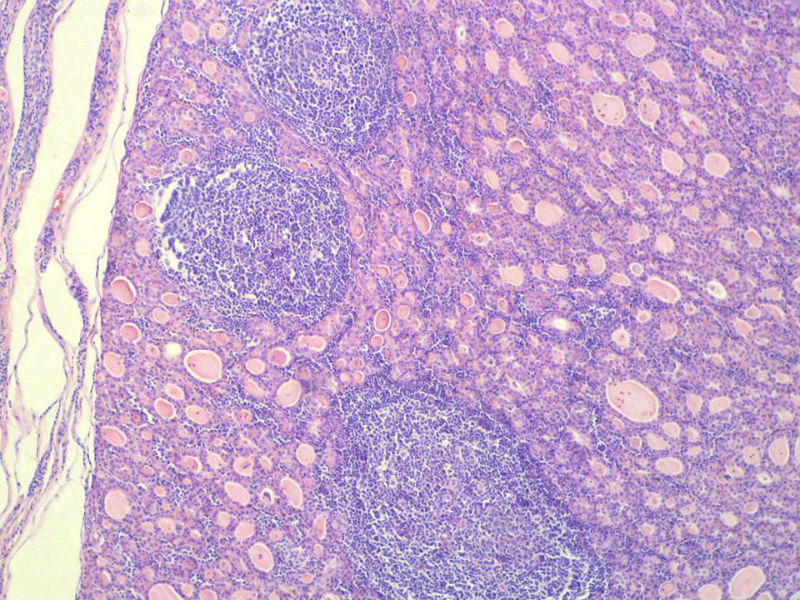

女,60岁,右侧甲状腺肿物两个月,术中见肿块与周围组织无粘连,肉眼,灰红色组织,3X2X2厘米,切面见一直径2.5厘米肿物,包膜完整,灰黄色,质软。

右侧甲状腺肿物图4

名称:图4

具有桥本氏病的大部分特征,有结节形成,此情况有称之为“结节性桥本甲状腺炎”